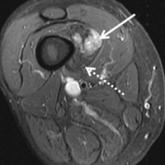

Multimodality Approach to a Stener Lesion: Radiographic, Ultrasound, Magnetic Resonance Imaging, and Surgical Correlation

The ulnar collateral ligament (UCL) of the thumb metacarpophalangeal joint is a static stabilizer that may rupture from a hyperabduction injury....